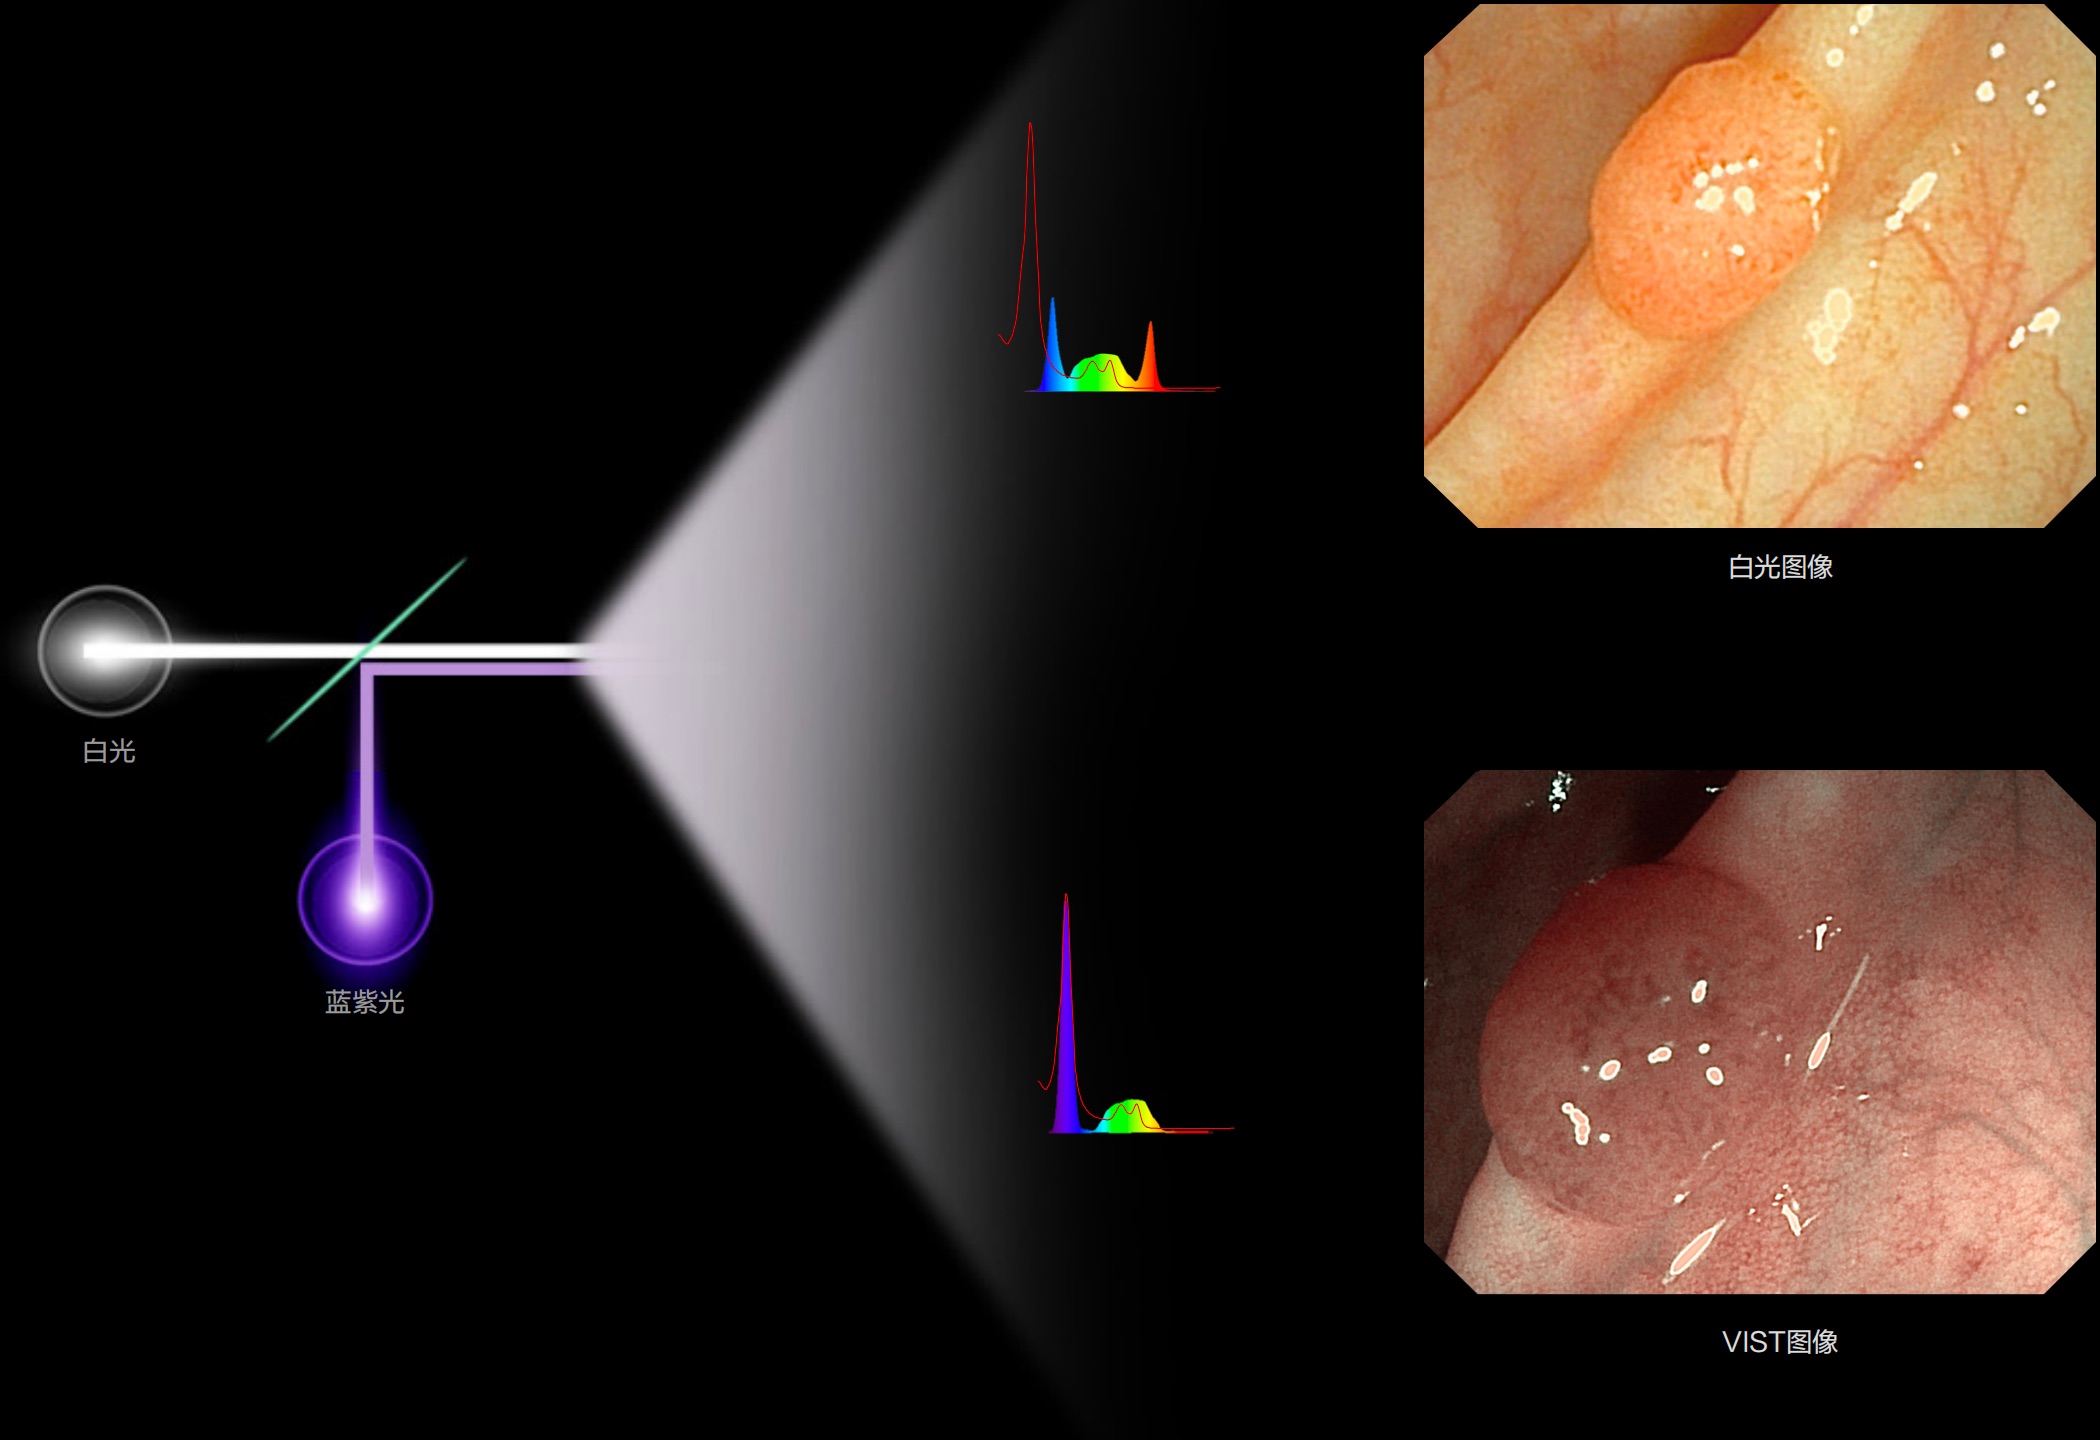

(Spectral Focused lmaging, SFI)

能够凸显黏膜浅层和中层血管轮廓,适用于中、远景观察下的病灶识别和早癌筛查。

照明光谱

光谱提取

光谱提取能量汇聚

RGB图像重建

染色模式显示

白光图像

SFI图像

(Versatile Intelligent Staining Technology)

能够凸显黏膜浅层血管轮廓和黏膜表面微结构,适用于中、近景观察下的早癌精确诊断。